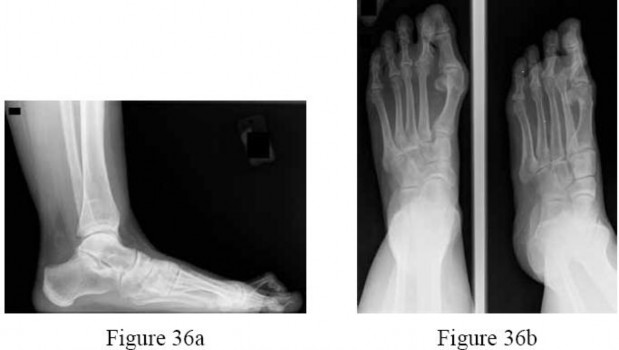

Question 10:

A 30-year-old female sustains a midfoot injury after falling from a horse. Radiographs demonstrate diastasis between the bases of the 1st and 2nd metatarsals. In a normal anatomic state, the native Lisfranc ligament originates and inserts on which two bony structures?

Correct Answer: Lateral aspect of the medial cuneiform to the medial aspect of the base of the 2nd metatarsal

Explanation:

The Lisfranc ligament is a stout, obliquely oriented intra-articular ligament that acts as the primary stabilizer of the second tarsometatarsal joint complex. It connects the lateral aspect of the medial cuneiform to the medial aspect of the base of the second metatarsal. Importantly, there is no direct ligamentous connection between the bases of the first and second metatarsals.